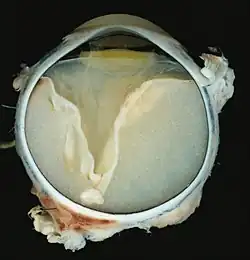

A case of Coats' disease, showing total retinal detachment with subretinal exudate containing cholesterol crystals and a fibrous nodule in the posterior pole

Grossly, retinal detachment and yellowish subretinal exudate containing cholesterol crystals are commonly seen.

A case of Coats' disease, showing total exudative retinal detachment, and subretinal exudate containing cholesterol crystals (H&E)

Microscopically, the wall of retinal vessels may be thickened in some cases, while in other cases the wall may be thinned with irregular dilatation of the lumen.[11] The subretinal exudate consists of cholesterol crystals, macrophages laden with cholesterol and pigment, erythrocytes, and hemosiderin.[12] A granulomatous reaction, induced by the exudate, may be seen with the retina.[13] Portions of the retina may develop gliosis as a response to injury.